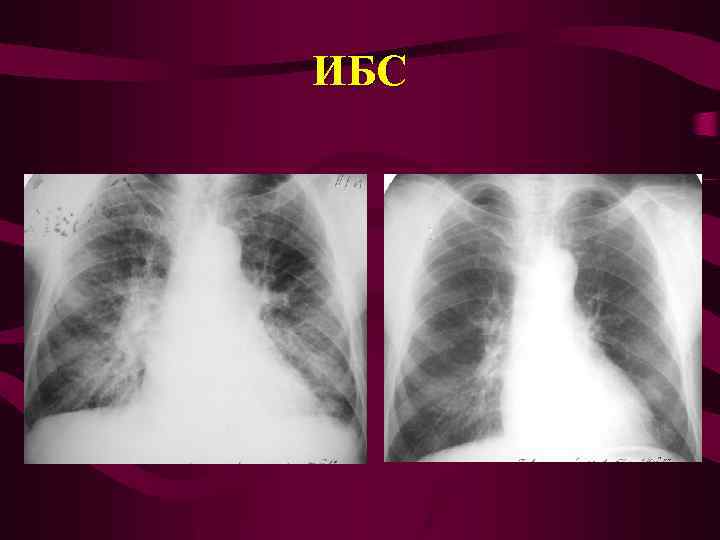

ИБС

ИБС

ИБС

ИБС

Ишемическая болезнь сердца • Стенокардия • Инфаркт миокарда • Постинфарктный кардиосклероз • Осложнения инфаркта миокарда

Ишемическая болезнь сердца • Стенокардия • Инфаркт миокарда • Постинфарктный кардиосклероз • Осложнения инфаркта миокарда